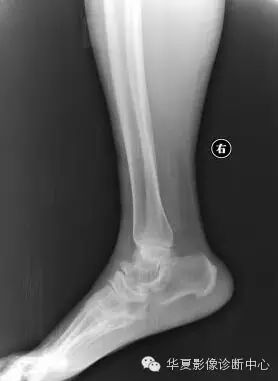

距骨嘴为距骨发育变异,常易被误诊为骨质增生及肿瘤。可引发一系列临床症状:不明原因的踝部“酸痛”,行走、站立常出现踝部酸胀感,时久甚之为主要症状。

主要体征:踝部软组织轻度肿胀、压痛,踝关节背屈、跖屈运动稍受限并症状有加重。可通过矫形外科治疗,切除后为正常骨性结构。

X线征象具有一定的特征性:

1、整个距骨形态呈“鸟头”状。

2、距骨颈短甚至消失。

3、“鸟头”具有一呈三角状向前突出的“鸟嘴”并具有正常的骨结构。

4、距骨头部与舟状骨关节接触面变小而呈圆弧性。